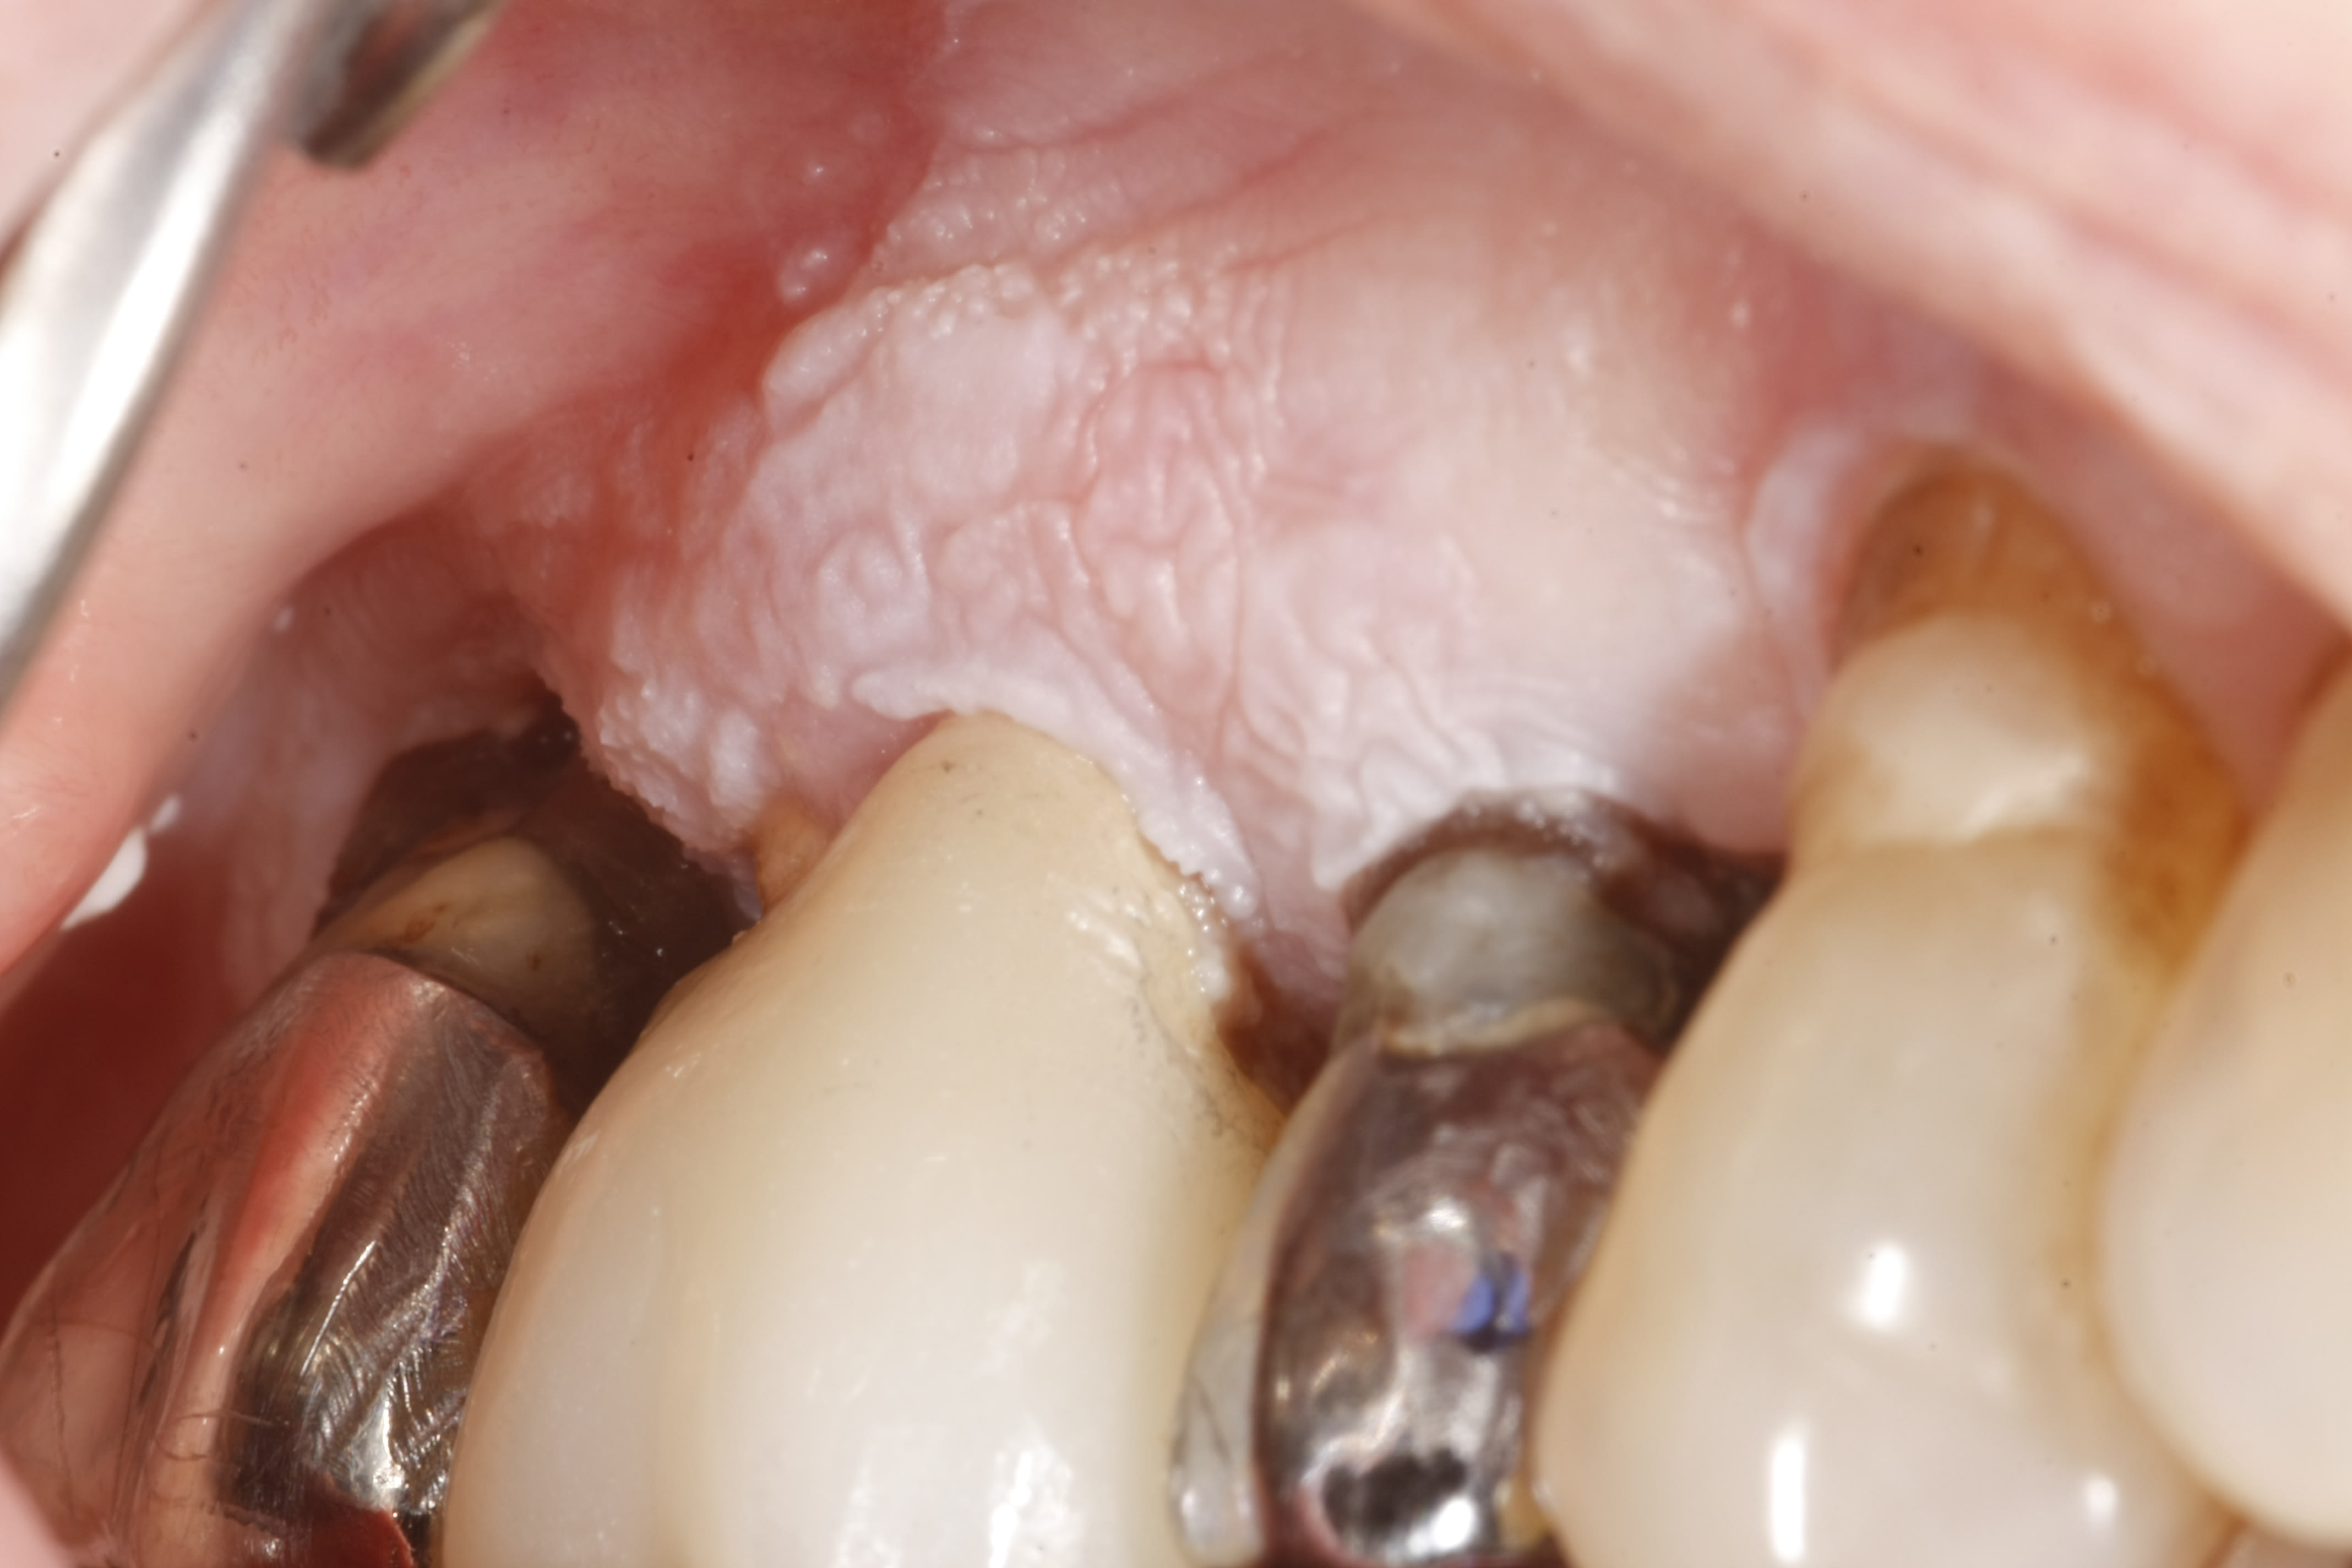

J'ai une charmante mamie de 84 ans avec une kératose chronique que j'ai du mal à identifier, et mes correspondants paro et stomato tout autant...

Lésion non détachable, apparue il y a 2 ans approximativement. L'étendue, la localisation varient peu au fil du temps. Les douleurs associées par contre, vont de "gêne" à "douloureux avec la brosse à dent 15/100ème" selon les moments.

Biopsie réalisée : Leucokératose isolée, sans malignité.

Dans les planches en cours de publication du Dr Lotfi Benslama et ses confrères, cela ressemble plus ou moins à :

Papillomatose orale floride

"L'âge de survenue des lésions est habituellement entre la sixième et la huitième décennie... La réalisation de biopsies multiples, fréquemment répétés, s'avère souvent nécessaire"